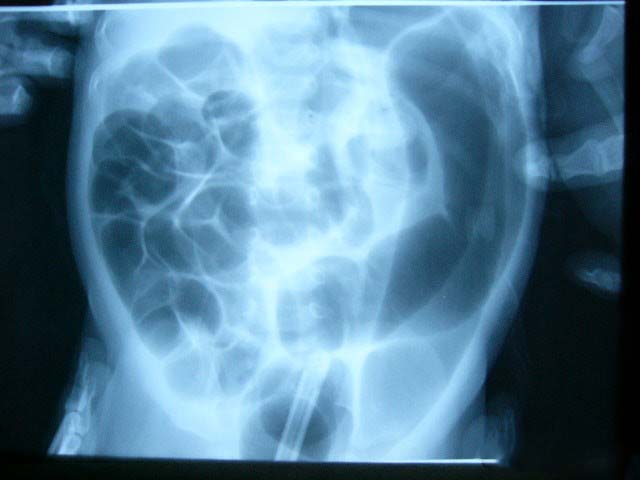

肠的痉挛性病变可累及小肠和大肠的任何部位。肠管的受累范围可局限于某一点,致肠管环状狭窄;偶尔也可同时累及肠道多处,形成多个节段性的狭窄;还可累及整个大肠,使其成为一条坚硬的索状物。最常受累的是大肠的降结肠和乙状结肠、小肠的末段回肠。痉挛的肠管常呈苍白、贫血状,肠管细小而变硬,与上、下正常肠管间有明显的分界线。如痉挛的时间较久,其近端肠腔可致继发性扩大、肥壁肥厚,其远端肠腔变小、肠壁变薄。